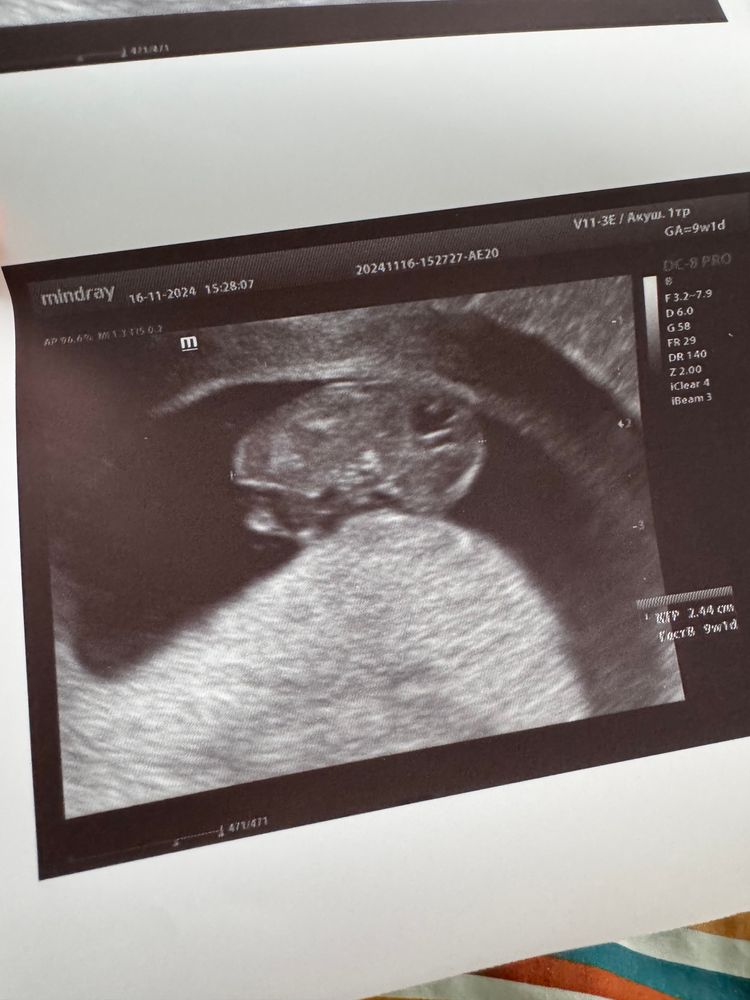

Полезла читать, ничего не нашла. На узи второй раз плодное яйцо вот такой колбасой (на 7 и 9 неделе). На 8 неделе была на узи у другого врача, оно было обычной округлой формы. Тонуса ни на одном узи не увидели. Спросила врача почему так, она сказала что кишечник давит на матку, то так, то сяк, это все норма. Как было у вас?

Анастасия, это уже третье😁 на втором у меня круглое было, на третьем вон опять колбаса) решила не обращать внимания